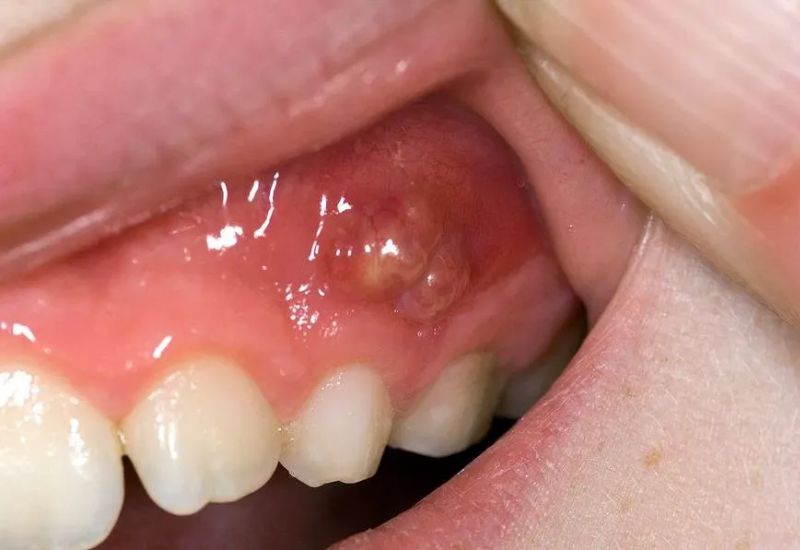

Áp xe lợi là tình trạng hình thành ổ mủ khu trú tại mô lợi do vi khuẩn gây nhiễm trùng. Ổ mủ này thường xuất hiện quanh răng, gây sưng đau, căng tức và có thể tiến triển nặng nếu không được điều trị kịp thời. Theo Healthline, áp xe lợi (còn gọi là áp xe nha chu) là một tình trạng đau đớn và có nguy cơ dẫn đến biến chứng nếu người bệnh chậm can thiệp y tế.

Nếu không được điều trị kịp thời, áp xe lợi có thể gây ra nhiều biến chứng nghiêm trọng. Tình trạng nhiễm trùng tại lợi có khả năng lan rộng sang các mô lân cận và các cơ quan khác trong cơ thể. Trong một số trường hợp hiếm gặp, nhiễm trùng kéo dài còn có thể dẫn đến nhiễm khuẩn huyết – một biến chứng nguy hiểm, đe dọa tính mạng.